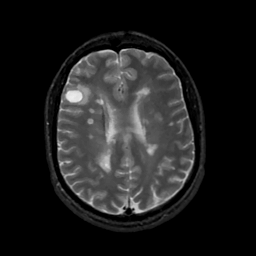

MR Study #7, March 24, 1991 -- Slice #32